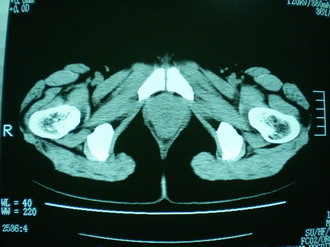

子宫增大,内可见类三角形低密度区,子宫后方可见类圆形团块状影,内部密度不均匀,可见靶样结构,结合病史考虑1子宫后方宫外孕(宫内假孕囊形成)2子宫肌瘤合并妊娠

子宫明显前倾,增大,宫颈增大呈分叶状。子宫直肠窝见不规则形水样低密度。(膀胱胀尿不理想)

考虑:1、宫颈部占位;

2、子宫直肠窝少量积液(盆腔炎所致)。

考虑:1、宫颈部占位(宫颈癌?);

2、子宫直肠窝少量积液。

1、前曲子宫,2、宫颈部占位?3、盆腔及右输卵管积液?宫内积血?4、左侧卵巢囊肿。